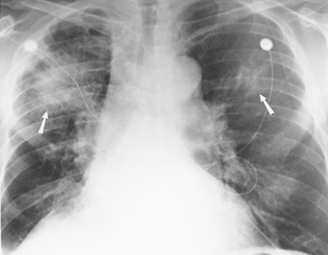

特发性间质性肺炎影像诊断